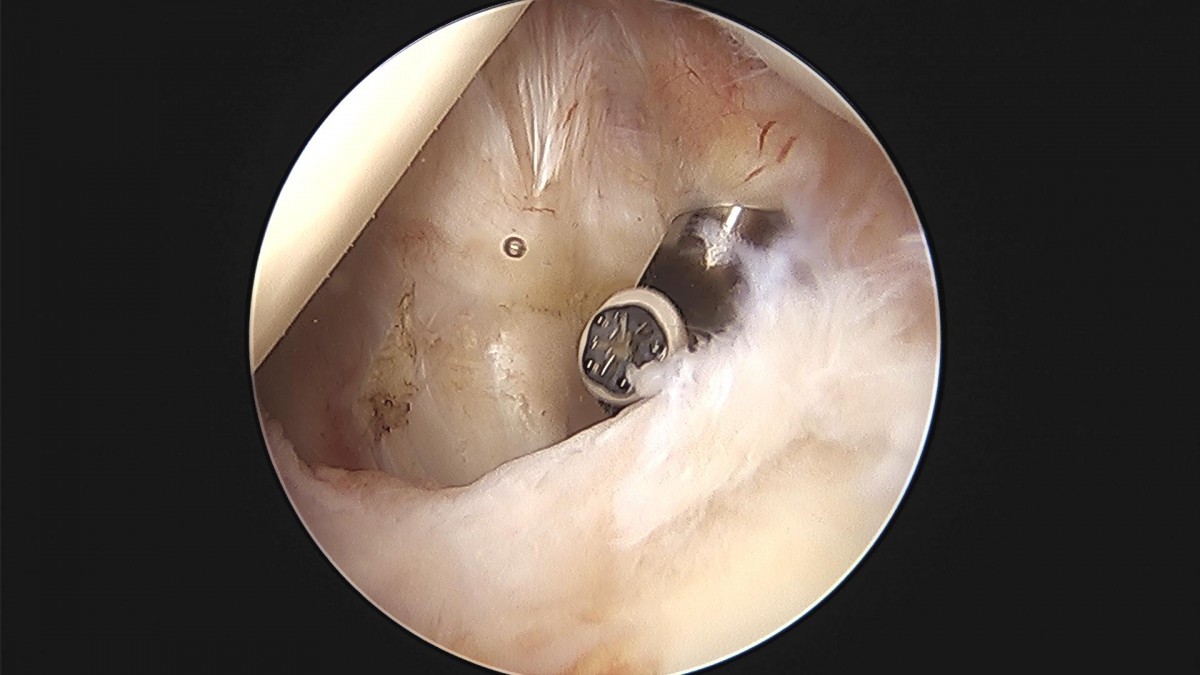

이재상 원장님 어깨 관절낭 이완술 및 견봉하 감압술 장정O 환자

작성자 최고관리자 댓글 0건 조회 857회 작성일 24-04-01 15:24